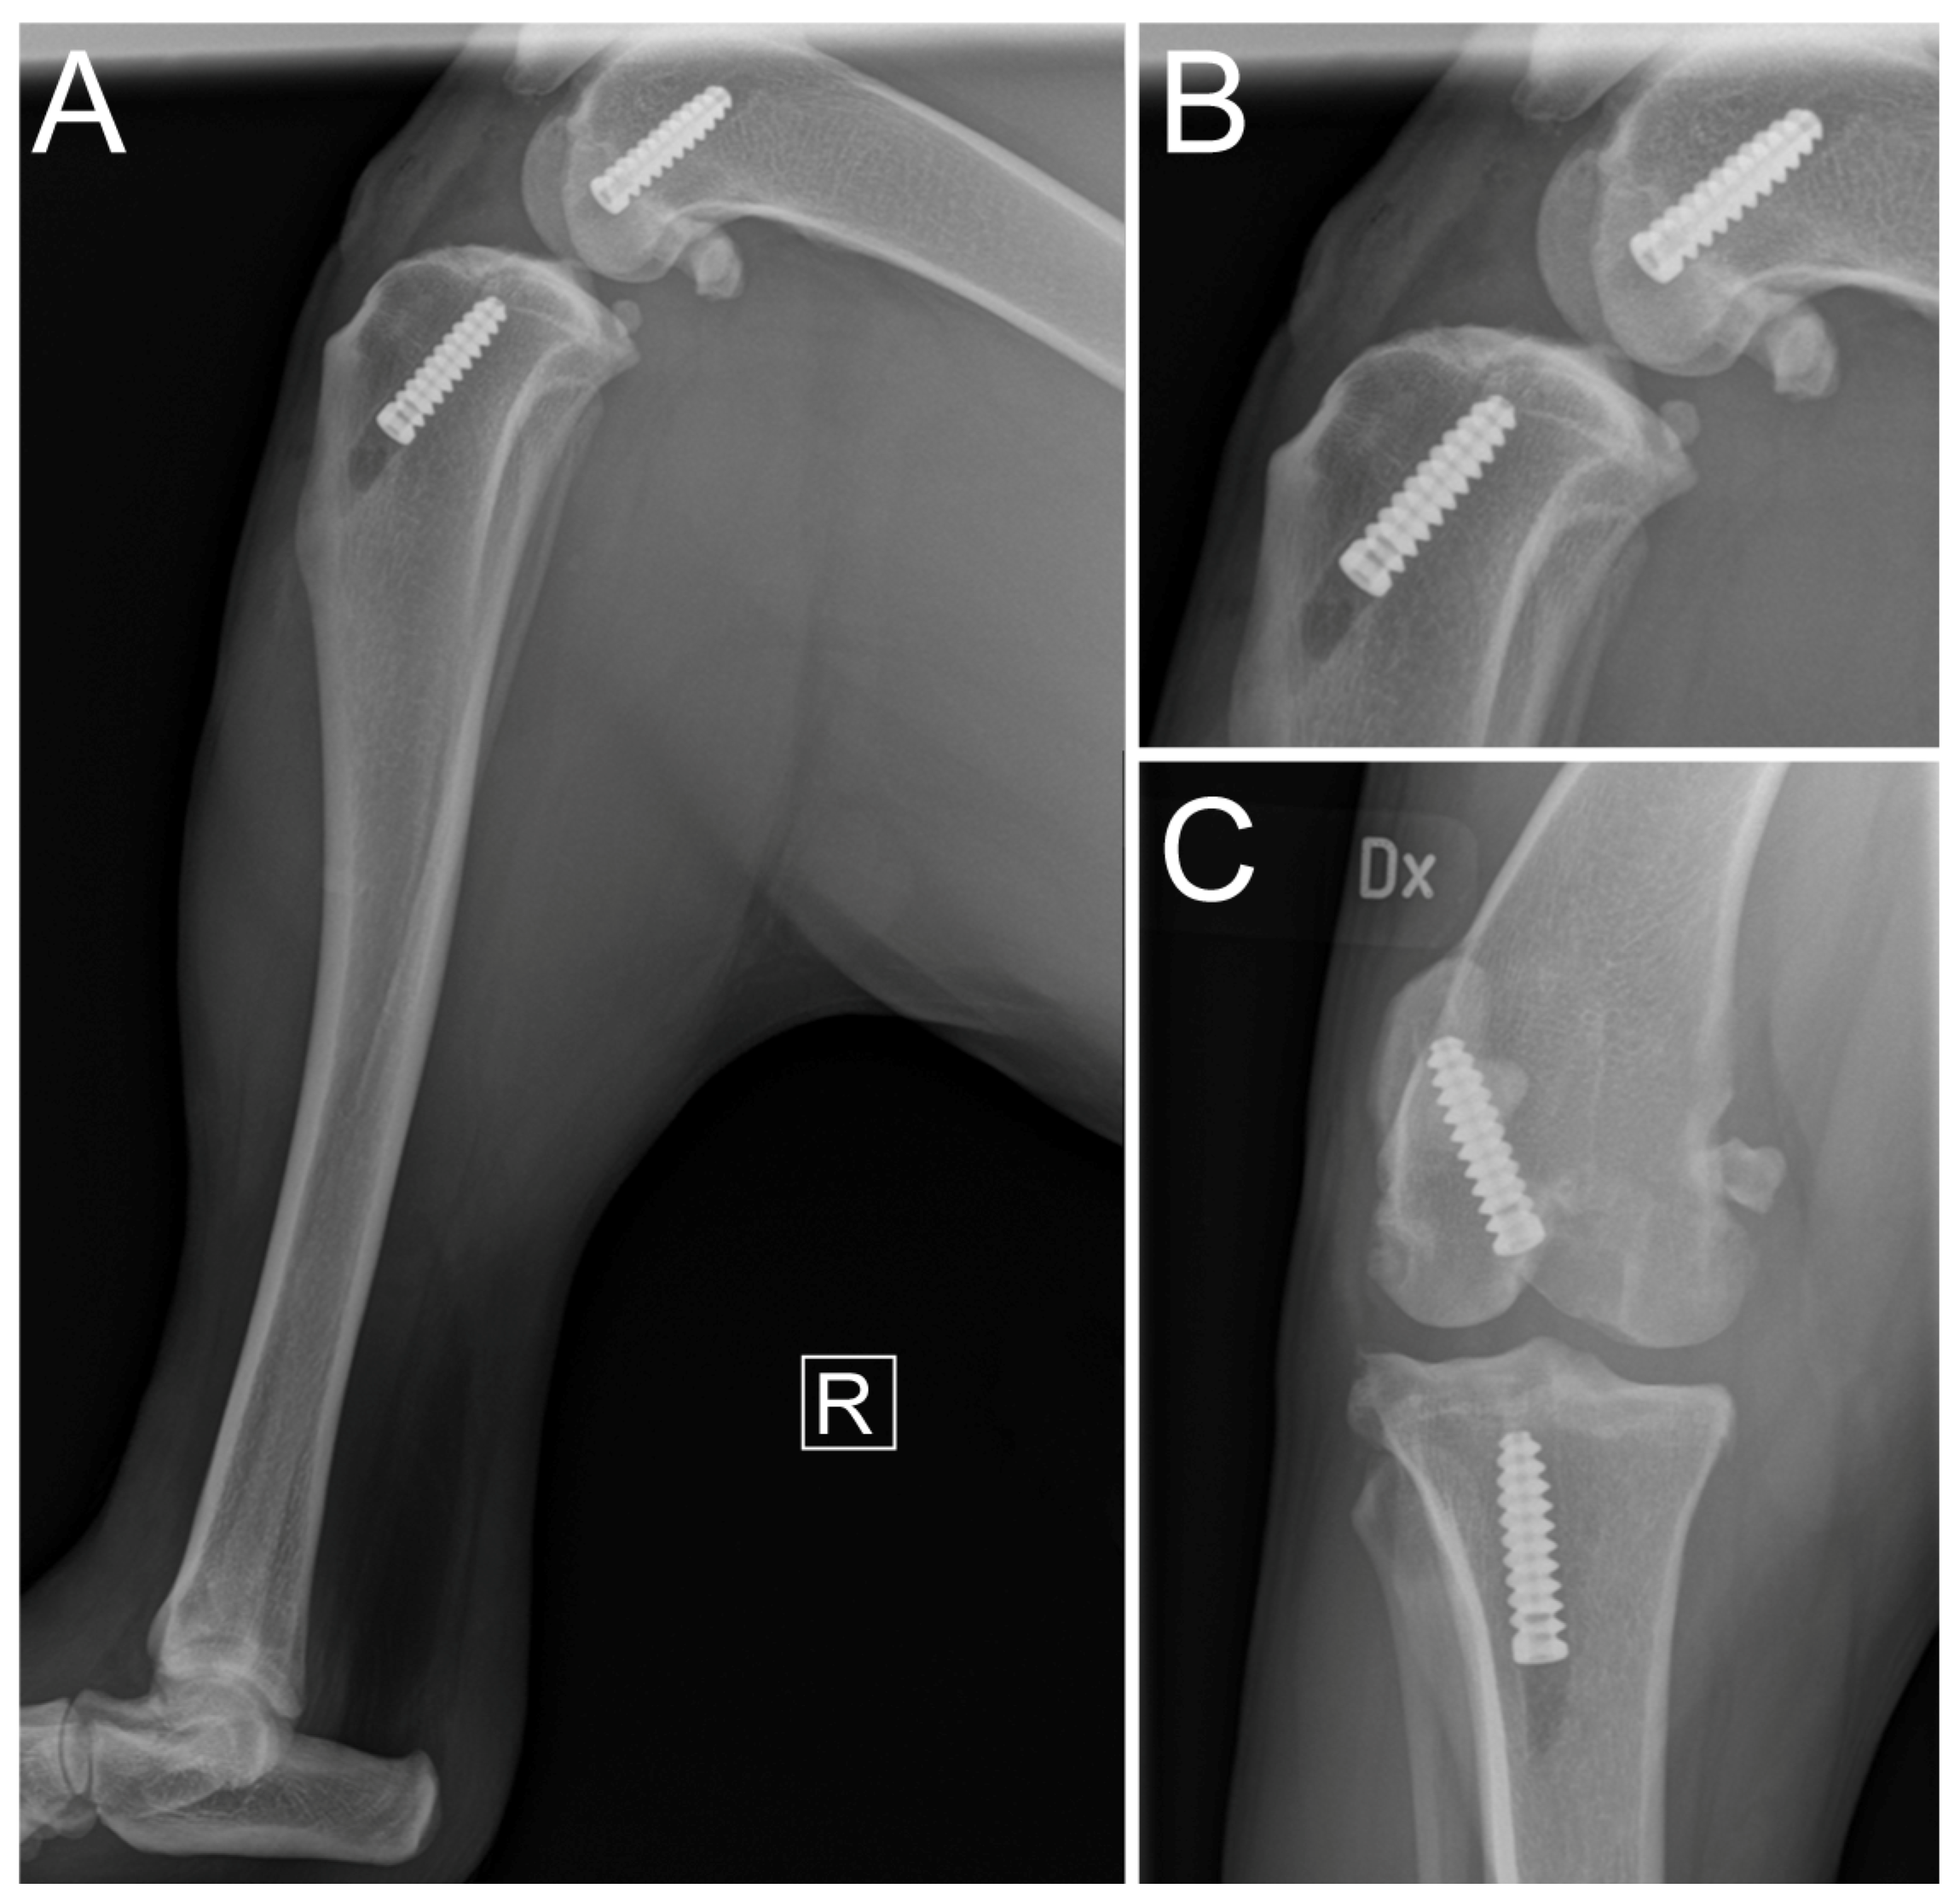

2.3. Diagnostic Imaging under Anesthesia

2.5. Immediate Postoperative Evaluation